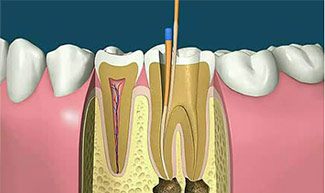

牙齿是由牙釉质、牙本质、牙髓、牙骨质、根管等多部分组合而成,当牙髓外露受到伤害的时候则需要进行治疗,其治疗的方法就是根管治疗。常 见的让牙髓外露的原因有蛀牙、外伤、牙齿断裂等,牙髓外露受到刺激,造成牙髓发炎坏死的过程就是产生牙齿疼痛的主要原因。受到牙痛困扰可 以选择根管治疗术进行治疗。

根管治疗术是治疗牙髓病及根尖周病较有效、快捷的方法,也是世上比较流行的先进治疗技术。它操作比较复杂,器械繁多而精细。根管治疗是针 对牙齿、牙髓、根尖病变等牙齿疾病的一个治疗过程。它通过清除根管内的坏死物质,进行适当的消毒,充填根管,以去除根管内容物对根尖周围 组织的不良刺激,防止发生根尖周病变或促进根尖周病变愈合的一种治疗方法。